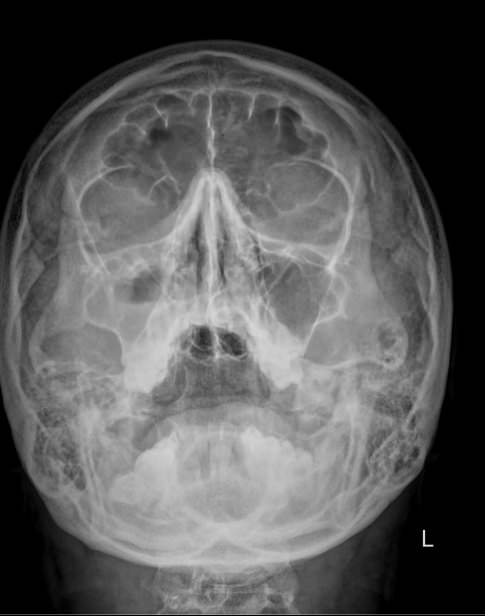

Предпочтительным методом диагностики искривления носовой перегородки является рентгенография. Это безболезненный, доступный и безопасный способ подтвердить искривление и определить его степень. Цифровая аппаратура последнего поколения испускает минимальную дозу излучения, сравнимую с естественным фоном.

Что покажет рентген костей носа при искривлении носовой перегородки

• Утолщение носовой перегородки;

• Искривление хрящевой части;

• Перелом костной части, в том числе со смещением;

• Новообразование, сдвигающее или разрушающее перегородку;

• Костные разрастания на прямой перегородке;

• Отек и воспаление мягких тканей.